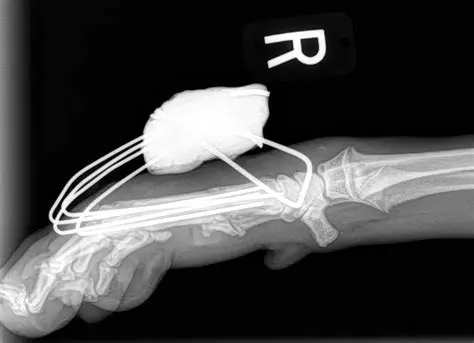

External Skeletal Fixators

ESFs are primarily used if there are open wounds which increases implant infection risk. All implants will ultimately be removed which eliminates this as a long-term issue. ESFs will also be used when patient size limits other implants or the fracture is very near a joint.

ESF configurations

Metacarpal fractures in a cat